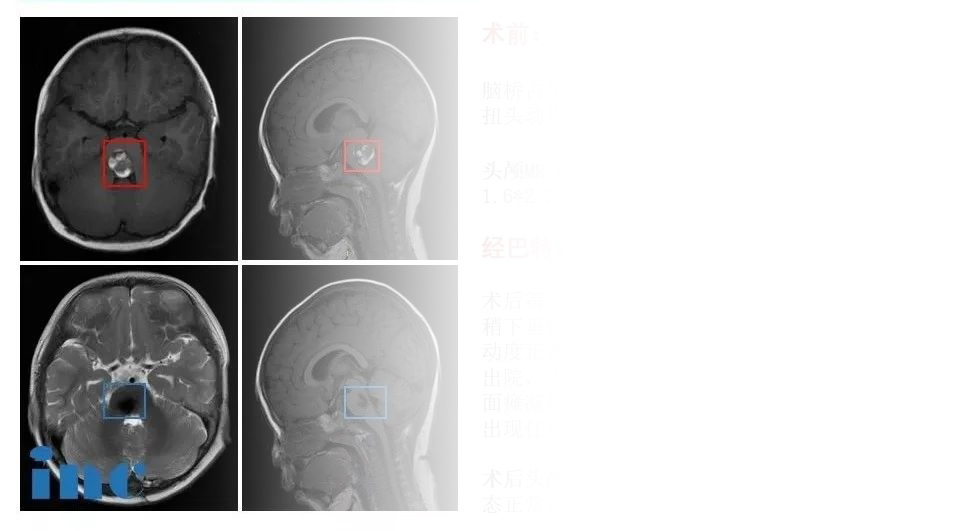

聪聪术前术后对比

近期聪聪较新的核磁结果也表明,孩子术后3年并没有复发迹象。术后3年里,聪聪术前产生的症状——眼球运动障碍、轻微面瘫、斜视、走路不稳等也完全已经恢复。

术后2天,经历了如此高难度手术的聪聪就出了ICU,他术前频发的不自主扭头动作都消失,左侧眼睑稍下垂较前开始好转,双眼斜视较前好转,眼球活动度正常,其他术前症状均出现缓慢好转。术后一周聪聪就出院了,术后一个半月复查,原有的斜视、走路不稳症状都消失了,面瘫减轻,行动能力完全正常,没出现任何新的并发症。现在,聪聪已经回归了原有的活力,而且今后不会再被这个疾病所折磨了,这是让聪聪父母无比欣慰和感恩的。